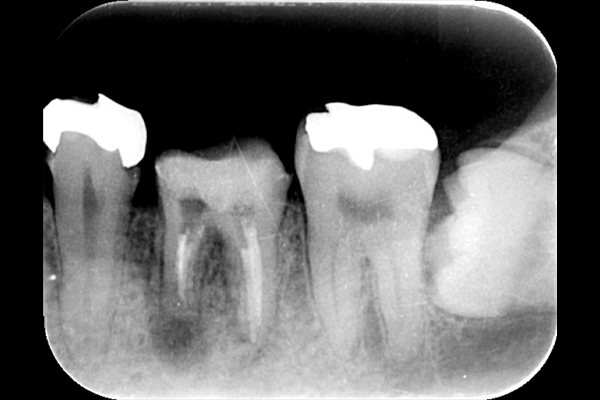

それは歯の先に枝分かれが多く存在し、そこにばい菌が入り込んで難治性となっているからです。ではその場合どうするのか?外科治療をします。その枝分かれの部分を切り落とすのです。今回はその前後のレントゲンの写真をお見せします。

| 根の中の薬が十分に充填されておらず、根の先が周りと比べて黒くなっており、炎症があると判断できます。 | 根の中にしっかりとお薬を緊密に充填しましたが、まだ根の先に黒くなっている部分があります。 |